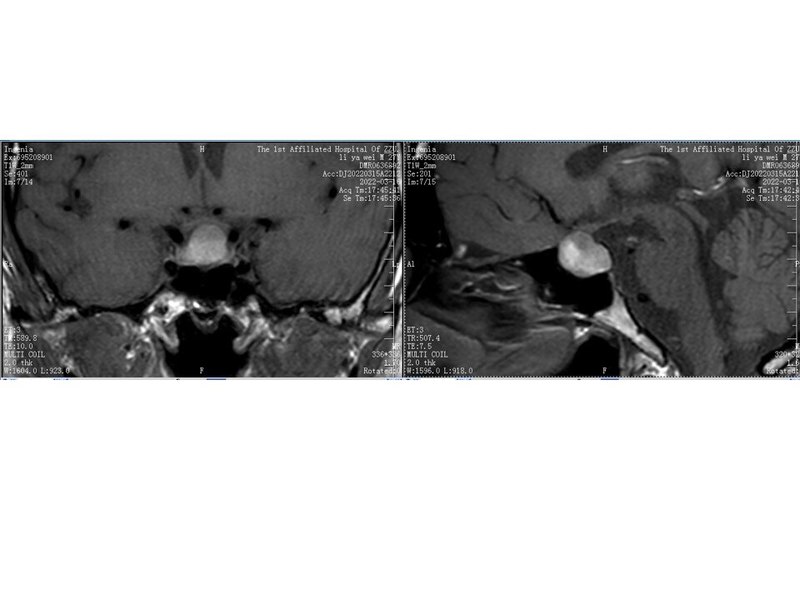

最近,完成內(nèi)鏡經(jīng)鼻切除垂體Rathke囊腫1例,介紹如下:患者42歲,男性,以“頭痛2年”為主訴入院。術(shù)前診斷為:垂體腺瘤合并卒中,術(shù)中所見考慮Rathke囊腫,術(shù)后病理支持。入院查MRI如下:垂體Rathke囊腫絕大多數(shù)居于鞍內(nèi),垂體前后葉之間,MRI檢查信號多變。一般患者有頭痛、視力視野改變,或者垂體激素異常,建議手術(shù)治療。完全位于鞍上、垂體柄內(nèi)的Rathke囊腫非常罕見。本病例豐富了對Rathke囊腫的認識,單純垂體柄內(nèi)病變,囊腫信號多變時,Rathke囊腫應(yīng)是一個考慮類型。